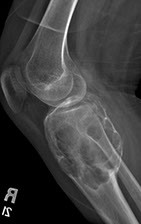

Osteoarthritis

Mechanical wear and tear of superficial articular cartilage with surface fibrillation (surface appears velvety), and then subchondral cysts, osteophytes (bone spurs, new bone and cartilage formation [from remodeling]), and eburnation (polished, ivory-like subchondral bone) once the articular cartilage is completely worn down

--sclerosis (has mature, lamellar architecture), NO ankylosis, Heberden's nodes (DIP), Bouchard's nodes

Imaging: osteophytes, sclerotic bone, joint space narrowing, subchondral bone cysts on xray

~ osteophytes: reactive bone formation at joint margin irritates synovial lining causing pain

~~ eventually bone rubs on bone, causing dense sclerosis

Micro: Vertical clefts / fibrillations in remaining cartilage

Articular surfaces missing from surfaces rubbing together, aka eburnation

Thickened areas of cancellous bone beneath eburnation

Microfracture of exposed articular bone

Previous fracture allows synovial fluid to enter, where it is walled off as a subchondral cyst